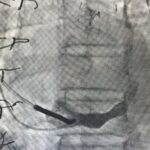

Zabieg wykonywany jest z nakłucia żyły szyjnej i polega na kontrolowanym zwężeniu zatoki wieńcowej przy użyciu rozprężalnego na balonie stentu o kształcie klepsydry. Wskutek zabiegu dochodzi do stopniowego zwężenia pola przepływu przez zatokę wieńcową z redystrybucją przepływu krwi z obszarów o lepszym do obszarów o gorszym ukrwieniu mięśnia sercowego.